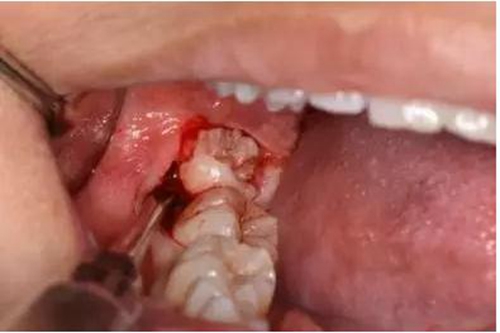

圖6. 從37頰側(cè)中份齦溝內(nèi)開始切開,向磨牙后區(qū)延伸

圖7.切開47遠(yuǎn)中齦溝并延長至磨牙后區(qū)約1cm。

圖10.普通牙挺放置在48牙冠的近中根面與牙槽嵴頂之間,采用推力和挺力,挺松48.